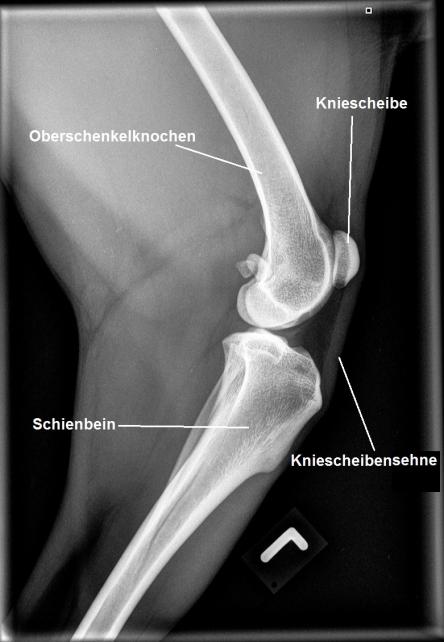

Erneut wird das verletzte Knie untersucht: Die beiden Hautwunden scheinen schön zu heilen, allerdings lässt sich nun feststellen, dass die Kniescheibensehne deutlich verdickt und schmerzhaft ist und sich weicher anfühlt als die Sehne im linken Knie. Die Patellarsehne (Ligamentum Patellae) zieht von der Kniescheibe zum Schienbein und ermöglicht dem Oberschenkelmuskel das Knie zu strecken. Röntgenaufnahmen der beiden Knie bestätigen, dass die Sehne stark verdickt ist. Unklar bleibt, ob sie gerissen oder nur stark überdehnt ist - in ersterem Fall muss das Problem zwingend chirurgisch angegangen werden. Wir überweisen Adlin deshalb zu einem MRT an eine Spezialistenklinik.

Für die Funktion des Hinterbeines ist die Sehne von zentraler Bedeutung: Sie überträgt die Kraft des grossen Oberschenkelmuskels (Quadriceps) via der "Umlenkrolle" Kniescheibe an den Schienbeinkopf und erlaubt so die Streckung des Knies. Reisst die Sehne, so ist der Hund nicht mehr in die Lage, über das Bein Kraft auszuüben, wodurch es funktionslos wird. In diesem Fall ist die chirurgische Reparatur des Risses zwingend.